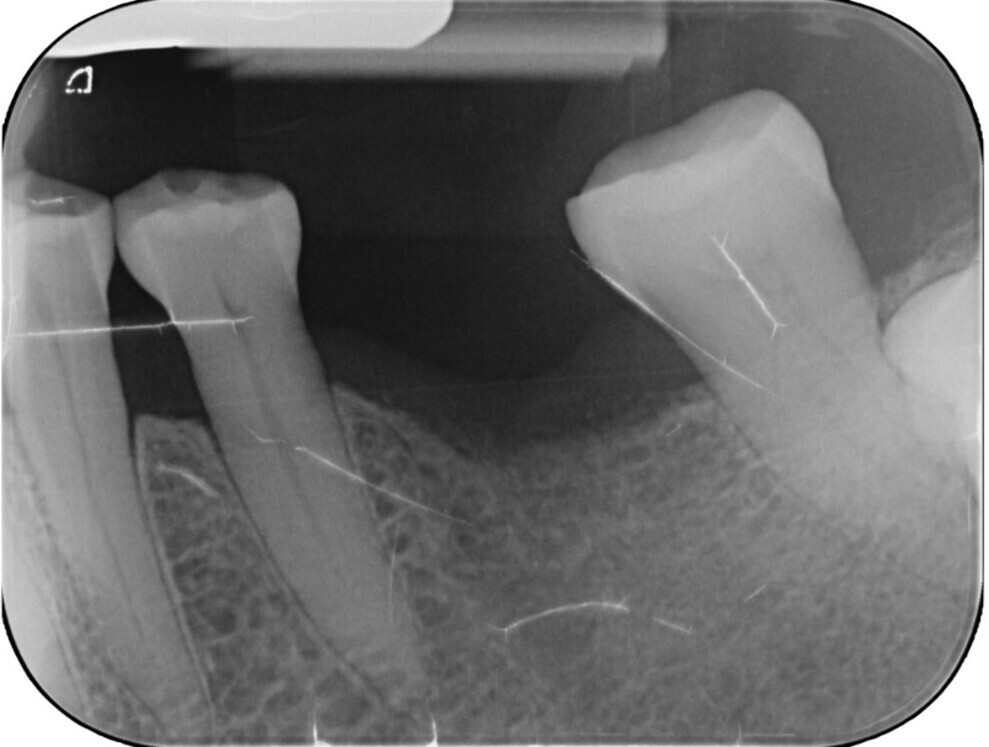

The prosthesis was permanently screwed into place using a calibrated torque wrench, and the screw access hole was sealed with PTFE tape and composite resin (Figs. 13 & 14). After a radiographic check of the treated area (Fig. 15), the patient was discharged with full function restored in a single session and reported high satisfaction with comfort and aesthetics.

Fig. 15: Radiographic evaluation of the restoration in place.